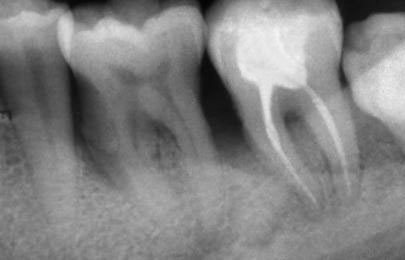

Рентгенографии на добре пролекувани зъби

При добре проведено ендодонтско лечение кореновият канал е запълнен точно до стеснението, разположено на 1 - 1.5 мм. от края на канала - т.нар. физиологично стеснение. Не бива да остава незапълнена част от канала. Много често се получава припресване на канлопълнежното средство извън канал на зъба, в тъканите около корена.